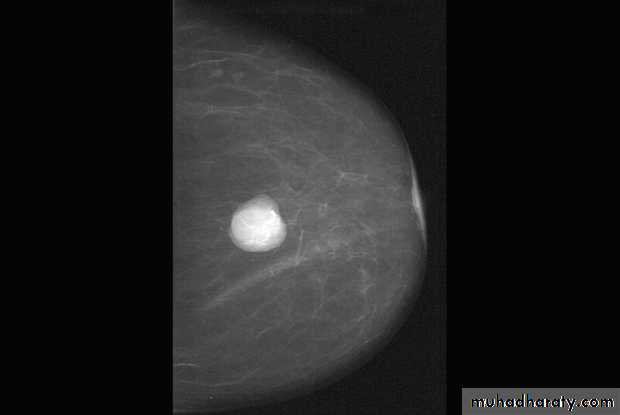

Benign calcification